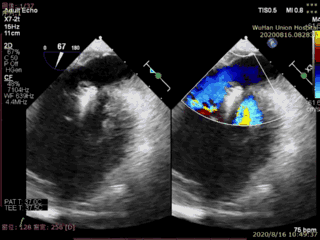

The patient in this case was an elderly male with multiple comorbidities. Preoperative echocardiography showed prolapse and flail of the posterior mitral leaflet (P2) accompanied by severe mitral regurgitation. The surgery was performed under transesophageal echocardiographic guidance, with the implantation of one Type IIIs mitral valve clip. Immediately after the surgery, mitral regurgitation disappeared, and the catheter operation time was less than 20 minutes, resulting in the successful completion of the surgery.

Postoperative echocardiogram